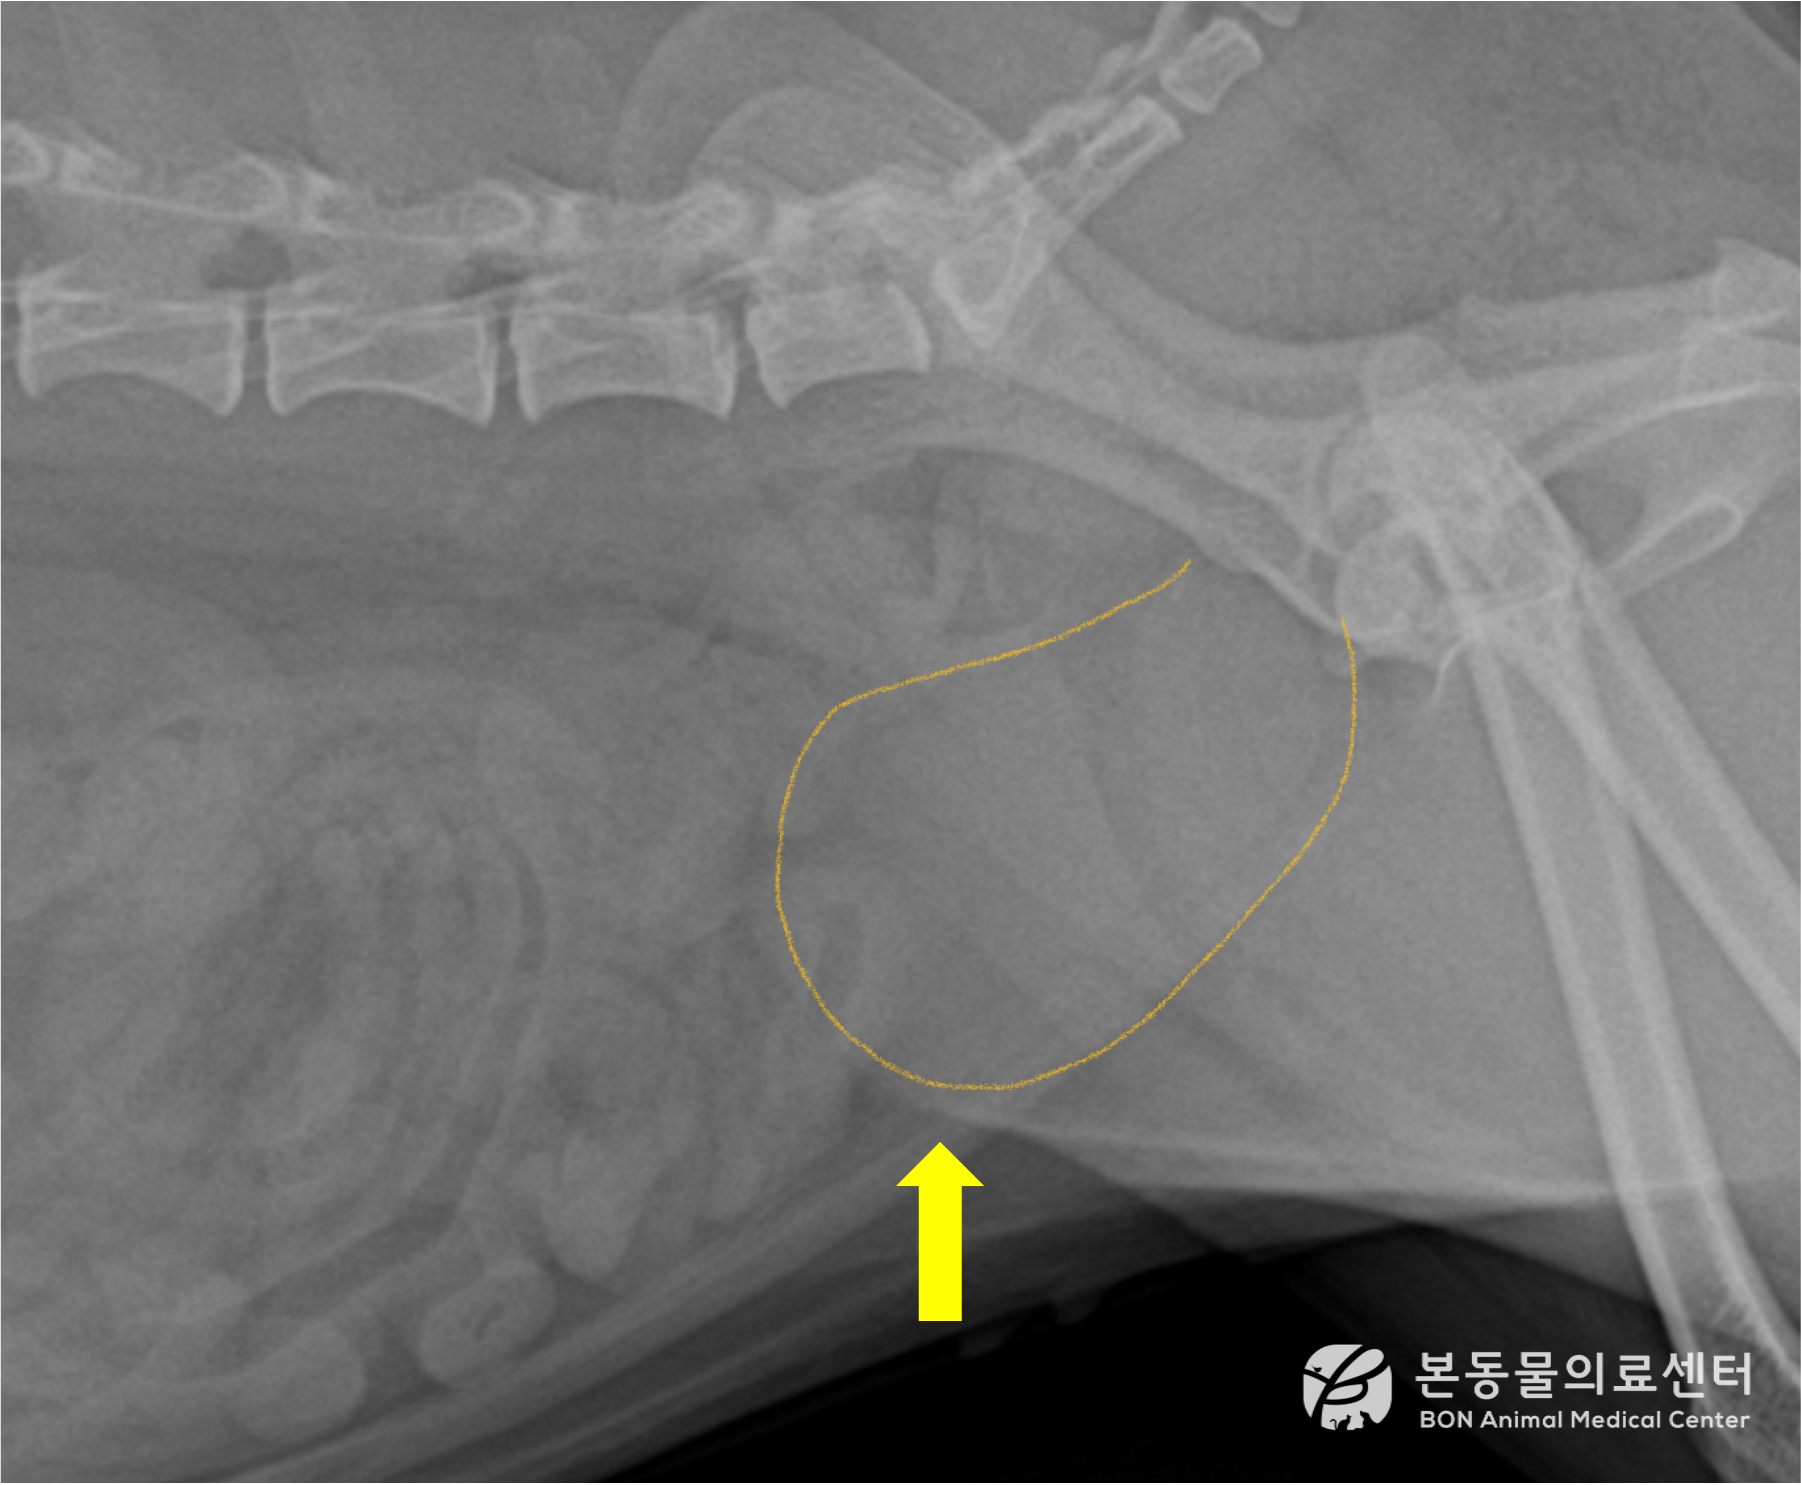

레이저 파쇄술 전 후 비교

<수술 후>